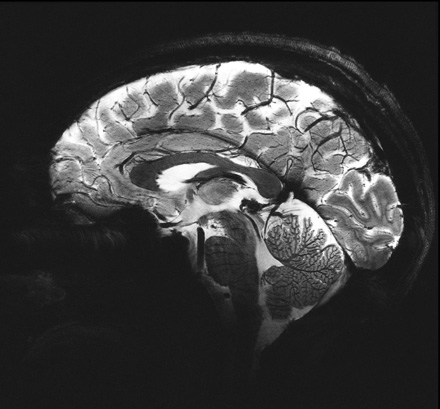

One of the first 11.7T images of the human brain recently acquired on a similar scanner at Neurospin in Paris. It has an in-plane resolution of just 200 microns.